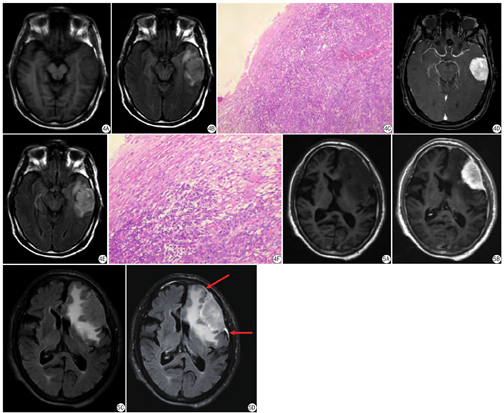

免疫组织化学染色检测标本中CD34的表达,一抗为兔抗人CD34单克隆抗体(1∶200)。CD34主要在细胞膜和细胞质,染色呈棕黄色颗粒者为阳性。先在低倍镜(×40)下确定脑膜瘤边缘部分,200倍显微镜下计算3个视野下的微血管数(见图1),求平均值。微血管数的具体判定方法:任何被染色为棕黄色的内皮细胞团或者单个内皮细胞都统计为一条独立的血管,是否形成管腔或有无红细胞存在不能成为判断标准,只要它们与邻近的肿瘤细胞、微血管以及其他结缔组织形成清楚的分隔,即是1个可计数的微血管。

在增强后T2 FLAIR上,62例(69.7%)脑膜瘤显示出周边弧线状强化,其中12例DSA证实为颅内外动脉双重血供(见图2)。25例患者术中肿瘤与脑实质的交界面表现为更多的粘连和出血倾向,术中可见颅内动脉血供为多。

在增强后T2 FLAIR上,62例(69.7%)脑膜瘤显示出周边弧线状高信号,其中25例病例仅在增强T2 FLAIR后显示该征象(在平扫T2 FLAIR序列或增强T1加权像上都未见该征象),该25例肿瘤术后HE染色可见肿瘤边缘部分、肿瘤与肿瘤表面的脑膜含有丰富微血管腔(见图3)。27例未显示出周边弧线形强化征的脑膜瘤中,肿瘤表面仅见少量血管和受压的蛛网膜(见图4)。

按照有无周边弧线形强化征分为4组(表1):①增强T1WI、增强T2 FLAIR可见;②仅增强T1 FLAIR可见;③仅增强T2 FLAIR可见;④增强T1WI、增强T2 FLAIR均不可见。每组MVD平均值先用用单样本非参数检验方法进行正态性检验。组②、组③、组④MVD数值都符合正态分布,用平均值±标准差表示;组①不符合正态分布,用中位数(四分位数间距)表示。组②、组④分别与组③两两采用两独立样本t检验统计方法;组①与组3进行Mann-Whitney非参数检验。统计结果如表1,表示4种不同类型的影像学表现均表现出脑膜瘤边缘MVD的不同情况。而且分组③仅增强后T2 FLAIR显示周边弧线形强化征的肿瘤边缘MVD计数明显大于分组④周边弧线形征阴性肿瘤边缘MVD。

| ①增强T1WI、增强T2 FLAIR可见 | 29 | 35.33(33.00,37.833) | <0.05 |

| ②仅增强T1WI可见 | 8 | 36.75±13.11 | <0.05 |

| ③仅增强T2 FLAIR可见 | 25 | 42.34±6.43 | N/A |

| ④增强T1WI、增强T2 FLAIR均不可见 | 27 | 21.52±6.71 | <0.05 |